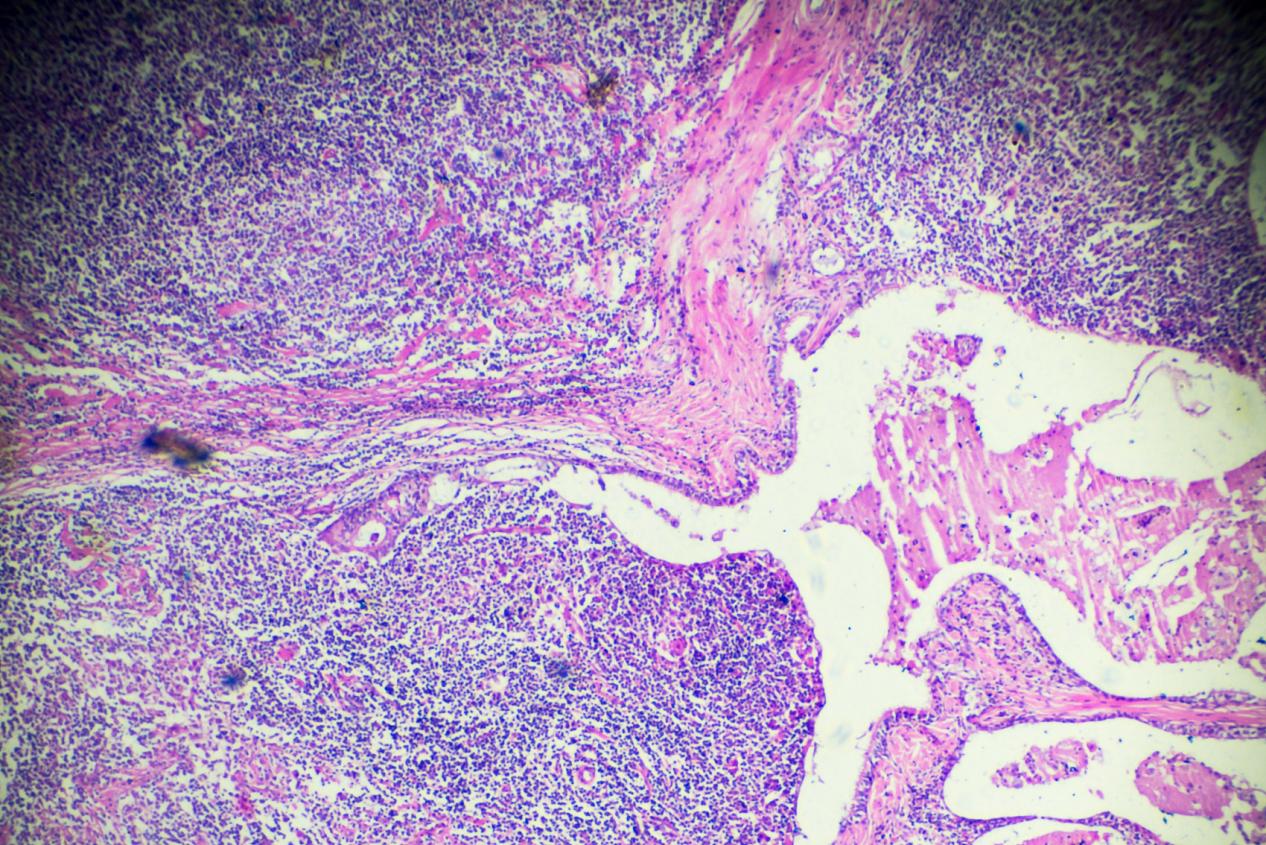

淋巴瘤的临床表现,昆明淋巴瘤医院哪家好-昆明医科肿瘤医院淋巴瘤是一类以淋巴细胞或淋巴组织为起始细胞的肿瘤,其临床表现因患者年龄、病理类型和病变部位等因素而异。以下是淋巴瘤可能出现的一些常见临床表现:淋巴结肿大:淋巴结是淋巴组织的一部分,淋巴瘤的最常见表现之一是...

淋巴瘤的概述,昆明淋巴瘤医院推荐哪家-昆明医科肿瘤医院淋巴瘤是一种源于淋巴系统的恶性肿瘤,它可以发生在身体任何部位的淋巴组织,包括淋巴结、脾脏、骨髓和其他淋巴器官。淋巴瘤是一种比较常见的肿瘤,它可以发生于任何年龄,但是在中年人和老年人中更为常见。淋巴瘤是由淋巴...

淋巴瘤的发病机制,昆明淋巴瘤医院排名哪家好-昆明医科肿瘤医院淋巴瘤是一种由淋巴细胞或浆细胞发生恶性转化导致的恶性肿瘤。淋巴瘤的发病机制是一个复杂的过程,涉及到多种因素的相互作用。本文将介绍淋巴瘤发病的几种常见机制。染色体异常染色体异常是淋巴瘤发生的常见机制之一...

淋巴瘤的病因,昆明淋巴瘤医院哪家好-昆明医科肿瘤医院淋巴瘤是一种由淋巴细胞或浆细胞发生恶性转化导致的恶性肿瘤。目前对于淋巴瘤的具体病因仍不是完全清楚的,但是已知有一些可能的因素会增加淋巴瘤的发生风险。免疫系统异常:免疫系统的异常功能可能会导致淋巴细胞的不正常增...